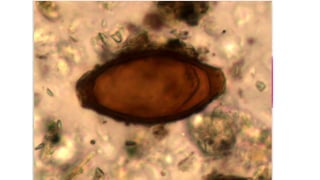

São platelmintos hermafroditas, que se reproduzem sexualmente. Se um

parasita adulto se reproduz no intestino de uma pessoa, seus ovos saem nas

fezes humanas e podem dar inicio ao ciclo da tênia.

A contaminação com ovos é mais séria: ingeridos em vegetais ou água, os

ovos liberam as larvas que fazem do corpo do homem um hospedeiro

intermediário. As larvas podem se instalar em diferentes partes do organismo,

levando em alguns casos até a morte. Essa doença é a cisticercose.

Verminoses Tênias Taenia solium: temos porcos como hospedeiro intermediário; Taenia saginata: tem os bovinos como hospedeiros intermediários. São platelmintos hermafroditas, que se reproduzem sexualmente. Se um parasita adulto se reproduz no intestino de uma pessoa, seus ovos saem nas fezes humanas e podem dar inicio ao ciclo da tênia. O contágio pela tênia adulta transforma a pessoa em um hospedeiro definitivo e ela desenvolve a doença chamada teníase.

Verminoses Tênias A contaminação comovos é mais séria: ingeridos em vegetais ou água, os ovos liberam as larvas que fazem do corpo do homem um hospedeiro intermediário. As larvas podem se instalar em diferentes partes do organismo, levando em alguns casos até a morte. Essa doença é a cisticercose.